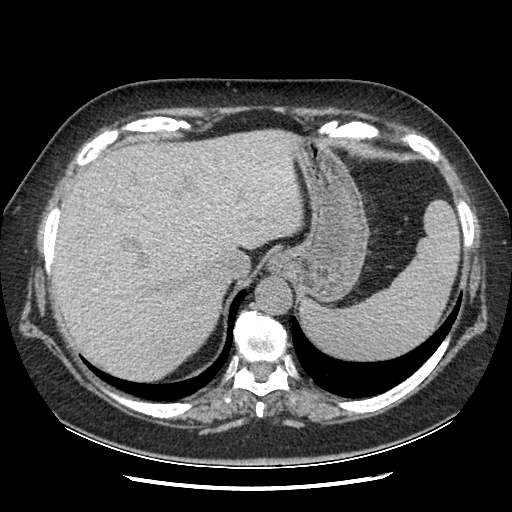

Original VENOUS CT scan

Full window (WL 1023.5, WW 4095 β†’ Low βˆ’1024, High +3071)

Lung window (WL -600, WW 1500 β†’ Low βˆ’1350, High +150)

Mediastinum window (WL 40, WW 400 β†’ Low βˆ’160, High +240)